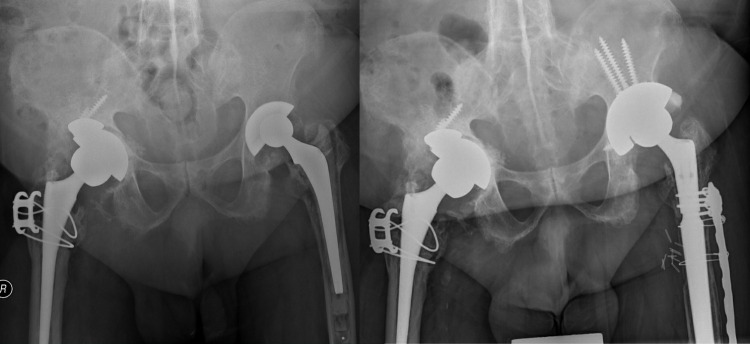

Methods: A total of 71 hips in 58 patients receiving the same model of cementless component without screw holes (Depuy Duraloc 100 hydroxyapatite (HA) component) from June 1999 to March 2003 were prospectively followed up. All patients were allowed to have immediate full weightbearing. The mean age at THA was 53.7 years (28 to 74). Osteonecrosis was the leading cause of THA. Survival was assessed with any revision and component revision as the endpoint. Radiological parameters, including lateral opening angle, and the components' vertical and horizontal migration distances, were measured and compared between the early postoperative period and final follow-up.

Results: Overall, 54 hips were assessed at a minimum 20-year follow-up. The mean follow-up was 22.9 years (20.9 to 24.5). Two component revisions occurred at 17.5 and 17.6 years later. Both components were well fixed but were revised, due to the need to upsize the articulation and component malpositioning, respectively. Conventional polyethylene (PE) was used in both hips, and 14 other hips were revised with the components well fixed and not revised. The estimated survival of the acetabular component and THA at 20 years was 96.4% and 74.5%, respectively. Mean changes in lateral opening angle and vertical and horizontal migration distances were 0.48° (SD 1.45°), -0.06 mm (SD 1.44), and -0.36 mm (SD 1.36), respectively, with no statistical significance.

Conclusion: This study provides evidence of excellent long-term survival of cementless components without screw holes. Immediate postoperative weightbearing did not lead to component migration in the long term.